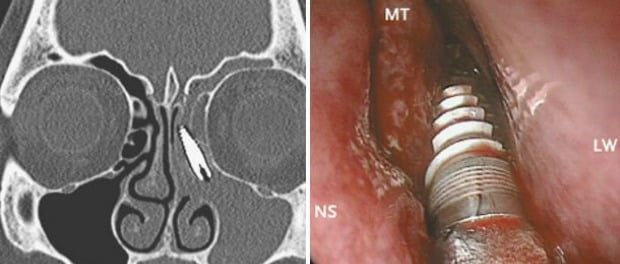

Médicos descobrem implante dentário em cavidade nasal